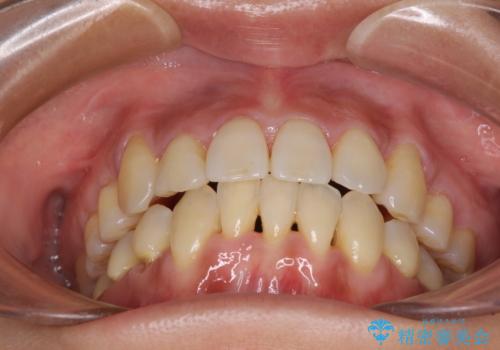

- 上下前歯のでこぼこを気にされ、矯正治療を希望された患者様です。

費用を抑えるため、メタルブラケットを採用し、抜歯矯正を行うこととしました。

通常であれば、上下顎左右小臼歯各1歯の合計4本を抜歯しますが、歯肉退縮の著しい下顎前歯を抜歯して欲しいという患者様の強い希望により、上顎のみ左右小臼歯2歯を、下顎は前歯を1歯を抜歯することとしました。

抜歯する歯を変更したため奥歯の咬合はアンバランスとなりましたが、前歯は綺麗に整い、歯肉退縮も回避できました。